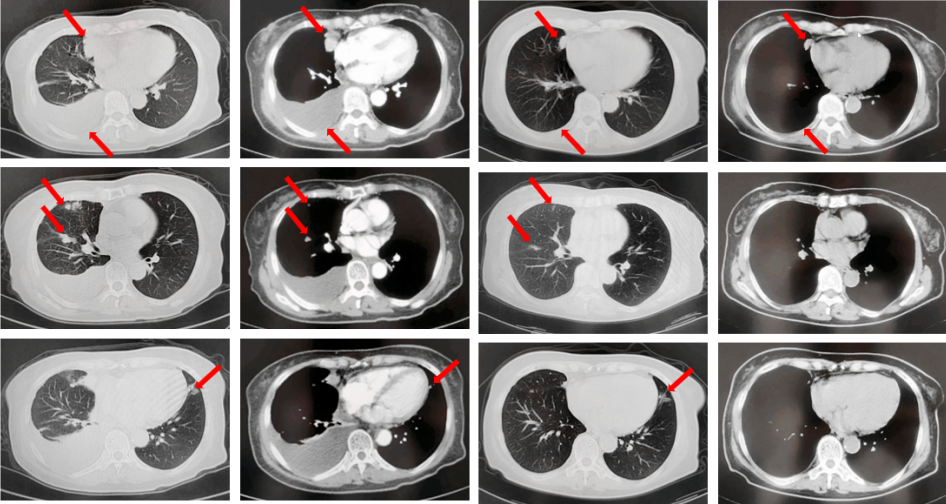

2022年7月至2022年11月行贝伐珠单抗联合培美曲塞/顺铂方案治疗6周期,2周期后评效PR,4周期后评效SD-(如图1)。第6周期治疗结束后患者自行终止治疗。

图1:由左至右分别展示基线(A.)及一线治疗后改变(B.和C.)。红色箭头指示病灶位置,由上至下分别为右肺肿物、右侧胸膜转移病灶及胸腔积液、左侧胸膜转移病灶、多发纵隔淋巴结肿大。